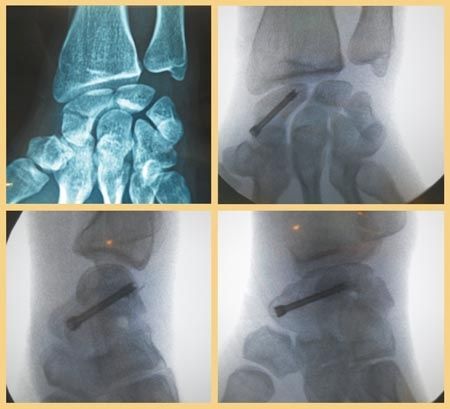

Technique Le vissage percutané rétrograde des fractures non ou peu déplacées du corp du scaphoïde , L. Thomsen Hôpital Saint Antoine - Paris N°206 - Août 2011 ● 13 min de lecture